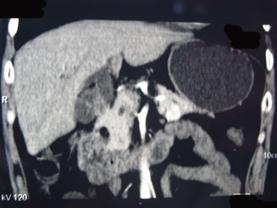

问题 男性,57岁,1年前无明显诱因反复出现嗜睡及发作性神志不清,进食糖水或甜品后症状即缓解,腹部CT检查如下图,最佳的诊断是()

选项 A.胰腺癌 B.胰岛细胞瘤 C.胰腺转移瘤 D.胃泌素瘤 E.舒血管活性肽瘤

答案 B